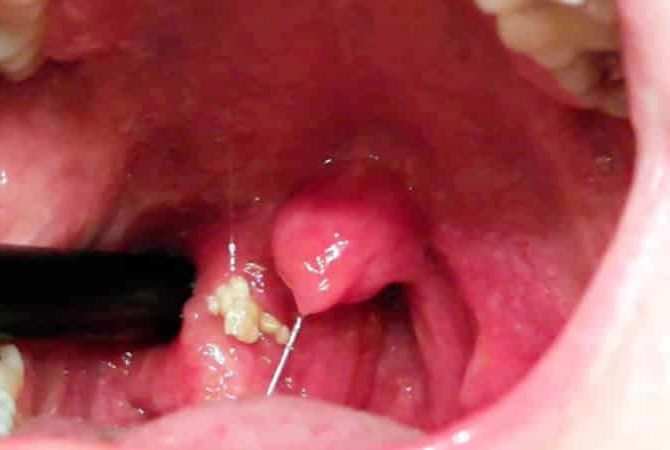

Що являють собою ці грудочки? Розташування цих грудок – лакуни мигдалин, їх ще називають гнійні освіти. Хронічне запалення піднебінних мигдалин або гостре запалення піднебінних мигдалин може спровокувати розвиток таких грудок.

Маленькі грудки, іноді потрапляють в рот при тих або інших обставинах, є нічим іншим, як тонзиллярными пробками або каменями, які формуються в спеціальних поглибленнях мигдалин – лакунах.

Як правило, люди зазначають білі, трохи рідше жовтуваті або навіть сіруваті погано пахнуть кульки. Іноді вони мають м’яку консистенцію, в інших випадках – досить щільну, що обумовлено присутністю в їх складі сполук кальцію.

Утворюються в лакунах мигдаликів білі грудочки формуються з постарілих і клітин клітин слизової оболонки, незначної кількості залишків з’їдених продуктів і різного роду бактерій.

Як правило, це стафілококи, стрептококи, дещо рідше хламідії та інші мікроорганізми, тобто в основному представники умовно-патогенної флори, яка постійно присутня в ротовій порожнині кожної людини.

Іноді до їх складу входить гній. У подібних ситуаціях вони набувають жовтий відтінок і характерний запах.

Білі грудки в горлі – це казеозные пробки в мигдалинах (тонзиллолиты).

Причина формування – хронічне запалення, як правило, розвивається після гострого тонзиліту (ангіни), який не був вилікуваний до кінця.

При хронічному тонзиліті хвороботворні бактерії продовжують жити і розмножуватися в лакунах мигдаликів. Тільки роблять це не так інтенсивно, як при гострому запаленні. Тим не менш, гній все одно формується.

Оскільки накопичення гнійних мас відбувається повільно, у них встигають відкластися мінеральні солі. В результаті пробки стають щільними. Їх навіть іноді називають камінням.

Медичне назва таких пробок – тонзиллолиты, що являє собою камені, що сформувалися в лакунах (мигдалини). Розмір таких грудочок може бути від одного міліметра до декількох сантиметрів.